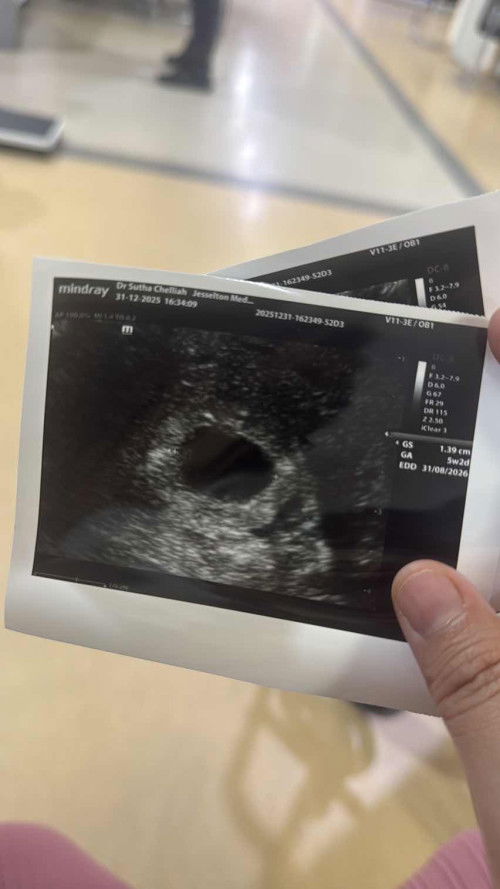

Scan tapi tak nampak yolk sac

ikut kiraan 6 weeks hari ni.. tapi tadi ada bleeding sikit since saya on crinone (ubat insert progestrone) so td doctor suspect pasal ubat tu luka sikit d serviks.. tp scan baru 5 weeks 2 days.. kantung nampak tp yolk sac xnampak… doktor suspect either x nampak lagi since masi awal atau blighted ovum… saya jadi 50/50.. takda cramping or bleeding dah skrg.. cuma jadi down sikit 😫